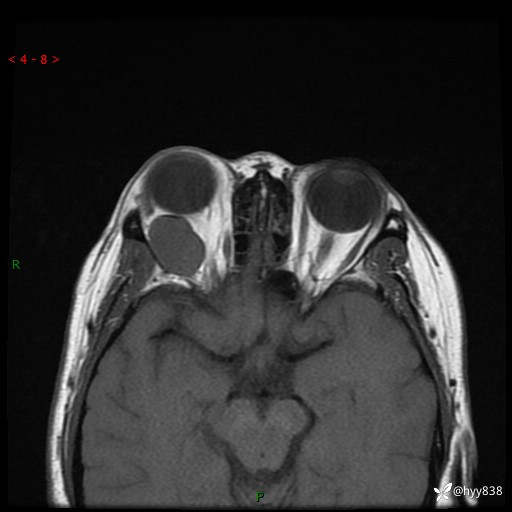

老年女性,右眼球突出1月。说说鉴别诊断,看谁第一个秒---(有结果)

主诉:发现右眼球突出1月余

简要病史:患者于1月前无明显诱因发现右眼球突出,偶感磨痛、眼胀,无视力下降,无头痛,恶心呕吐等不适。10天前就诊于当地县人民医院就诊,完善头颅ct检查,诊断为右侧眼眶肿物,建议患者上级医院进一步治疗,患者因个人原因拒绝。拟行手术,来我院就诊,门诊行相关检查后以“右眼眼眶肿物”收入院。 患病以来,患者精神饮食睡眠尚可,大小便如常、体重无明显改变。

辅助检查:MRI

临床诊断:眼眶肿物

眼眶MRI平扫+增强